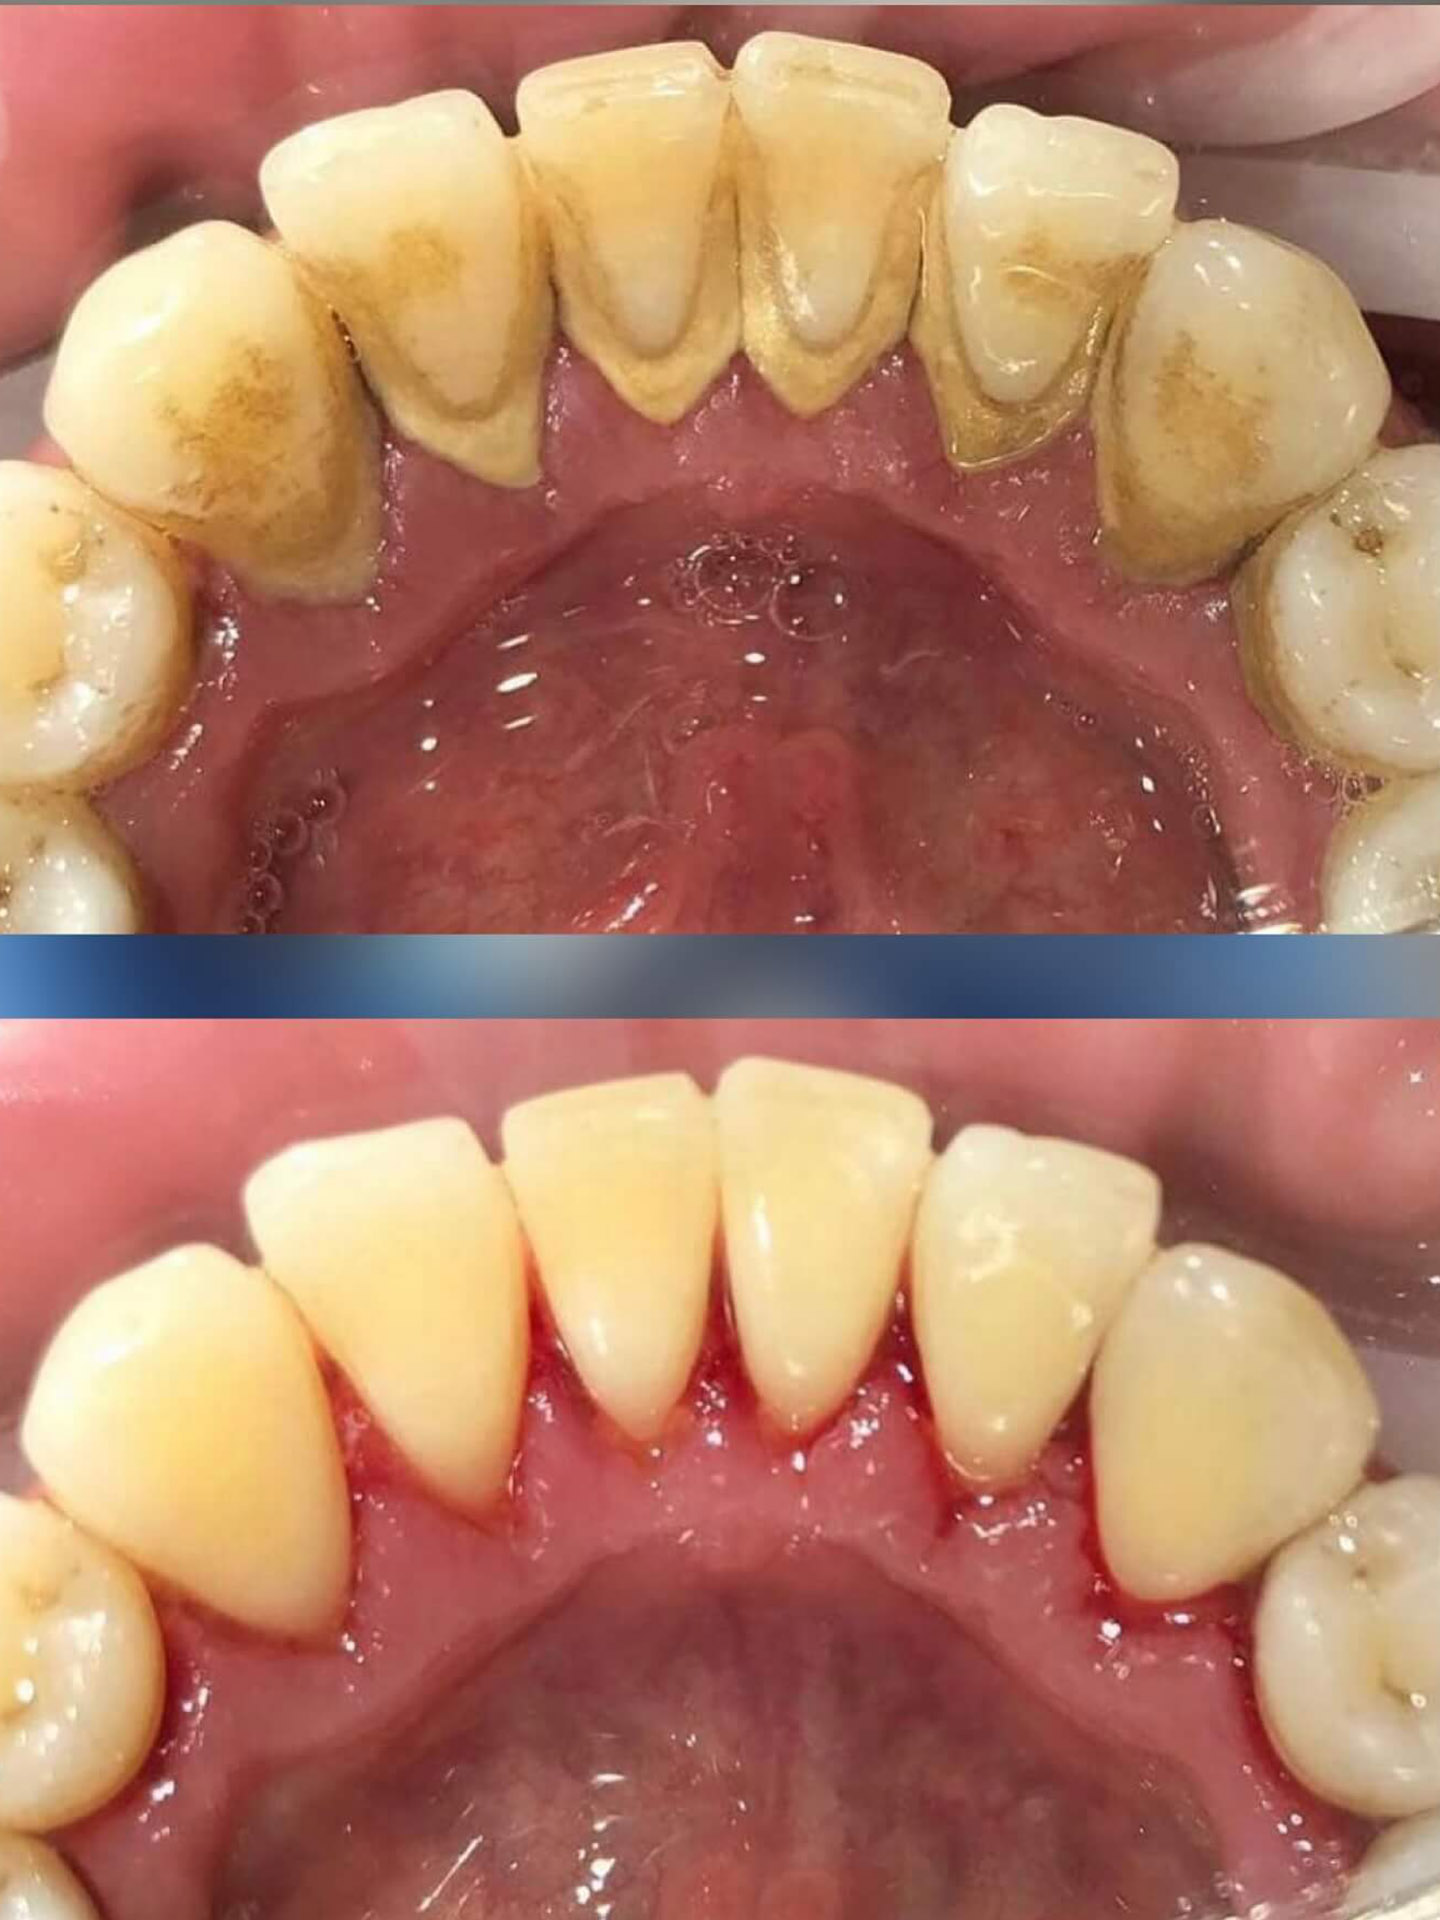

Înainte și după tratament

Dr. Ungureanu Dr. Ungureanu